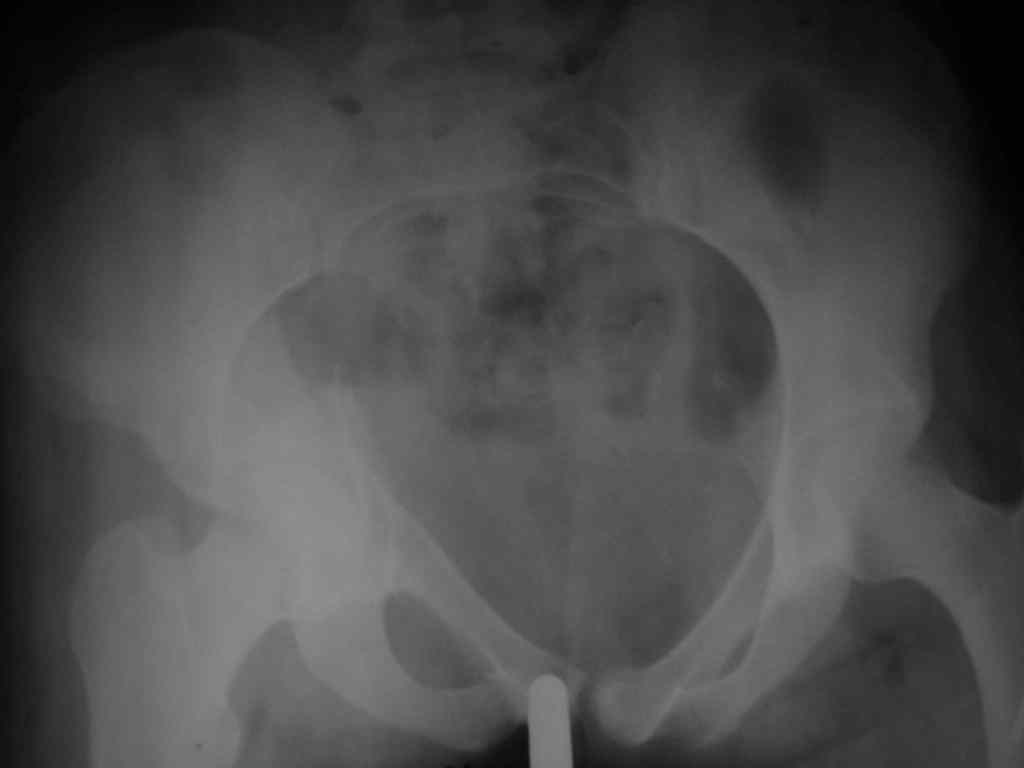

Здравствуйте, коллеги! 27/01/07 в отделение поступила девушка с множественным переломом костей таза справа с нарушением тазового кольца, ротационная нестабильность (седалищная, лонная кости, крыло подвздошной кости, перелом дна вертлужной впадины) и закрытый перелом обеих костей голени справа. При поступлении наложена система скелетного вытяжения за пяточную кость справа. Проведена противошоковая терапия. Состояние в данный момент стабильное. Планируется оперативное лечение перелома костей голени в наших условиях и наложение системы скелетного вытяжения за правое бедро на этой неделе. Просим рассмотреть вариант оперативного лечения травмы таза в условиях УНИИТО.

Здравствуйте, коллеги. У больной имеется высокий двухколонный перелом. Суставная поверхность скорее всего разошлась не сильно (Сделайте запирательную проекцию). Смущает обратная клиновидность щели сустава и укорочение при молодом возрасте.